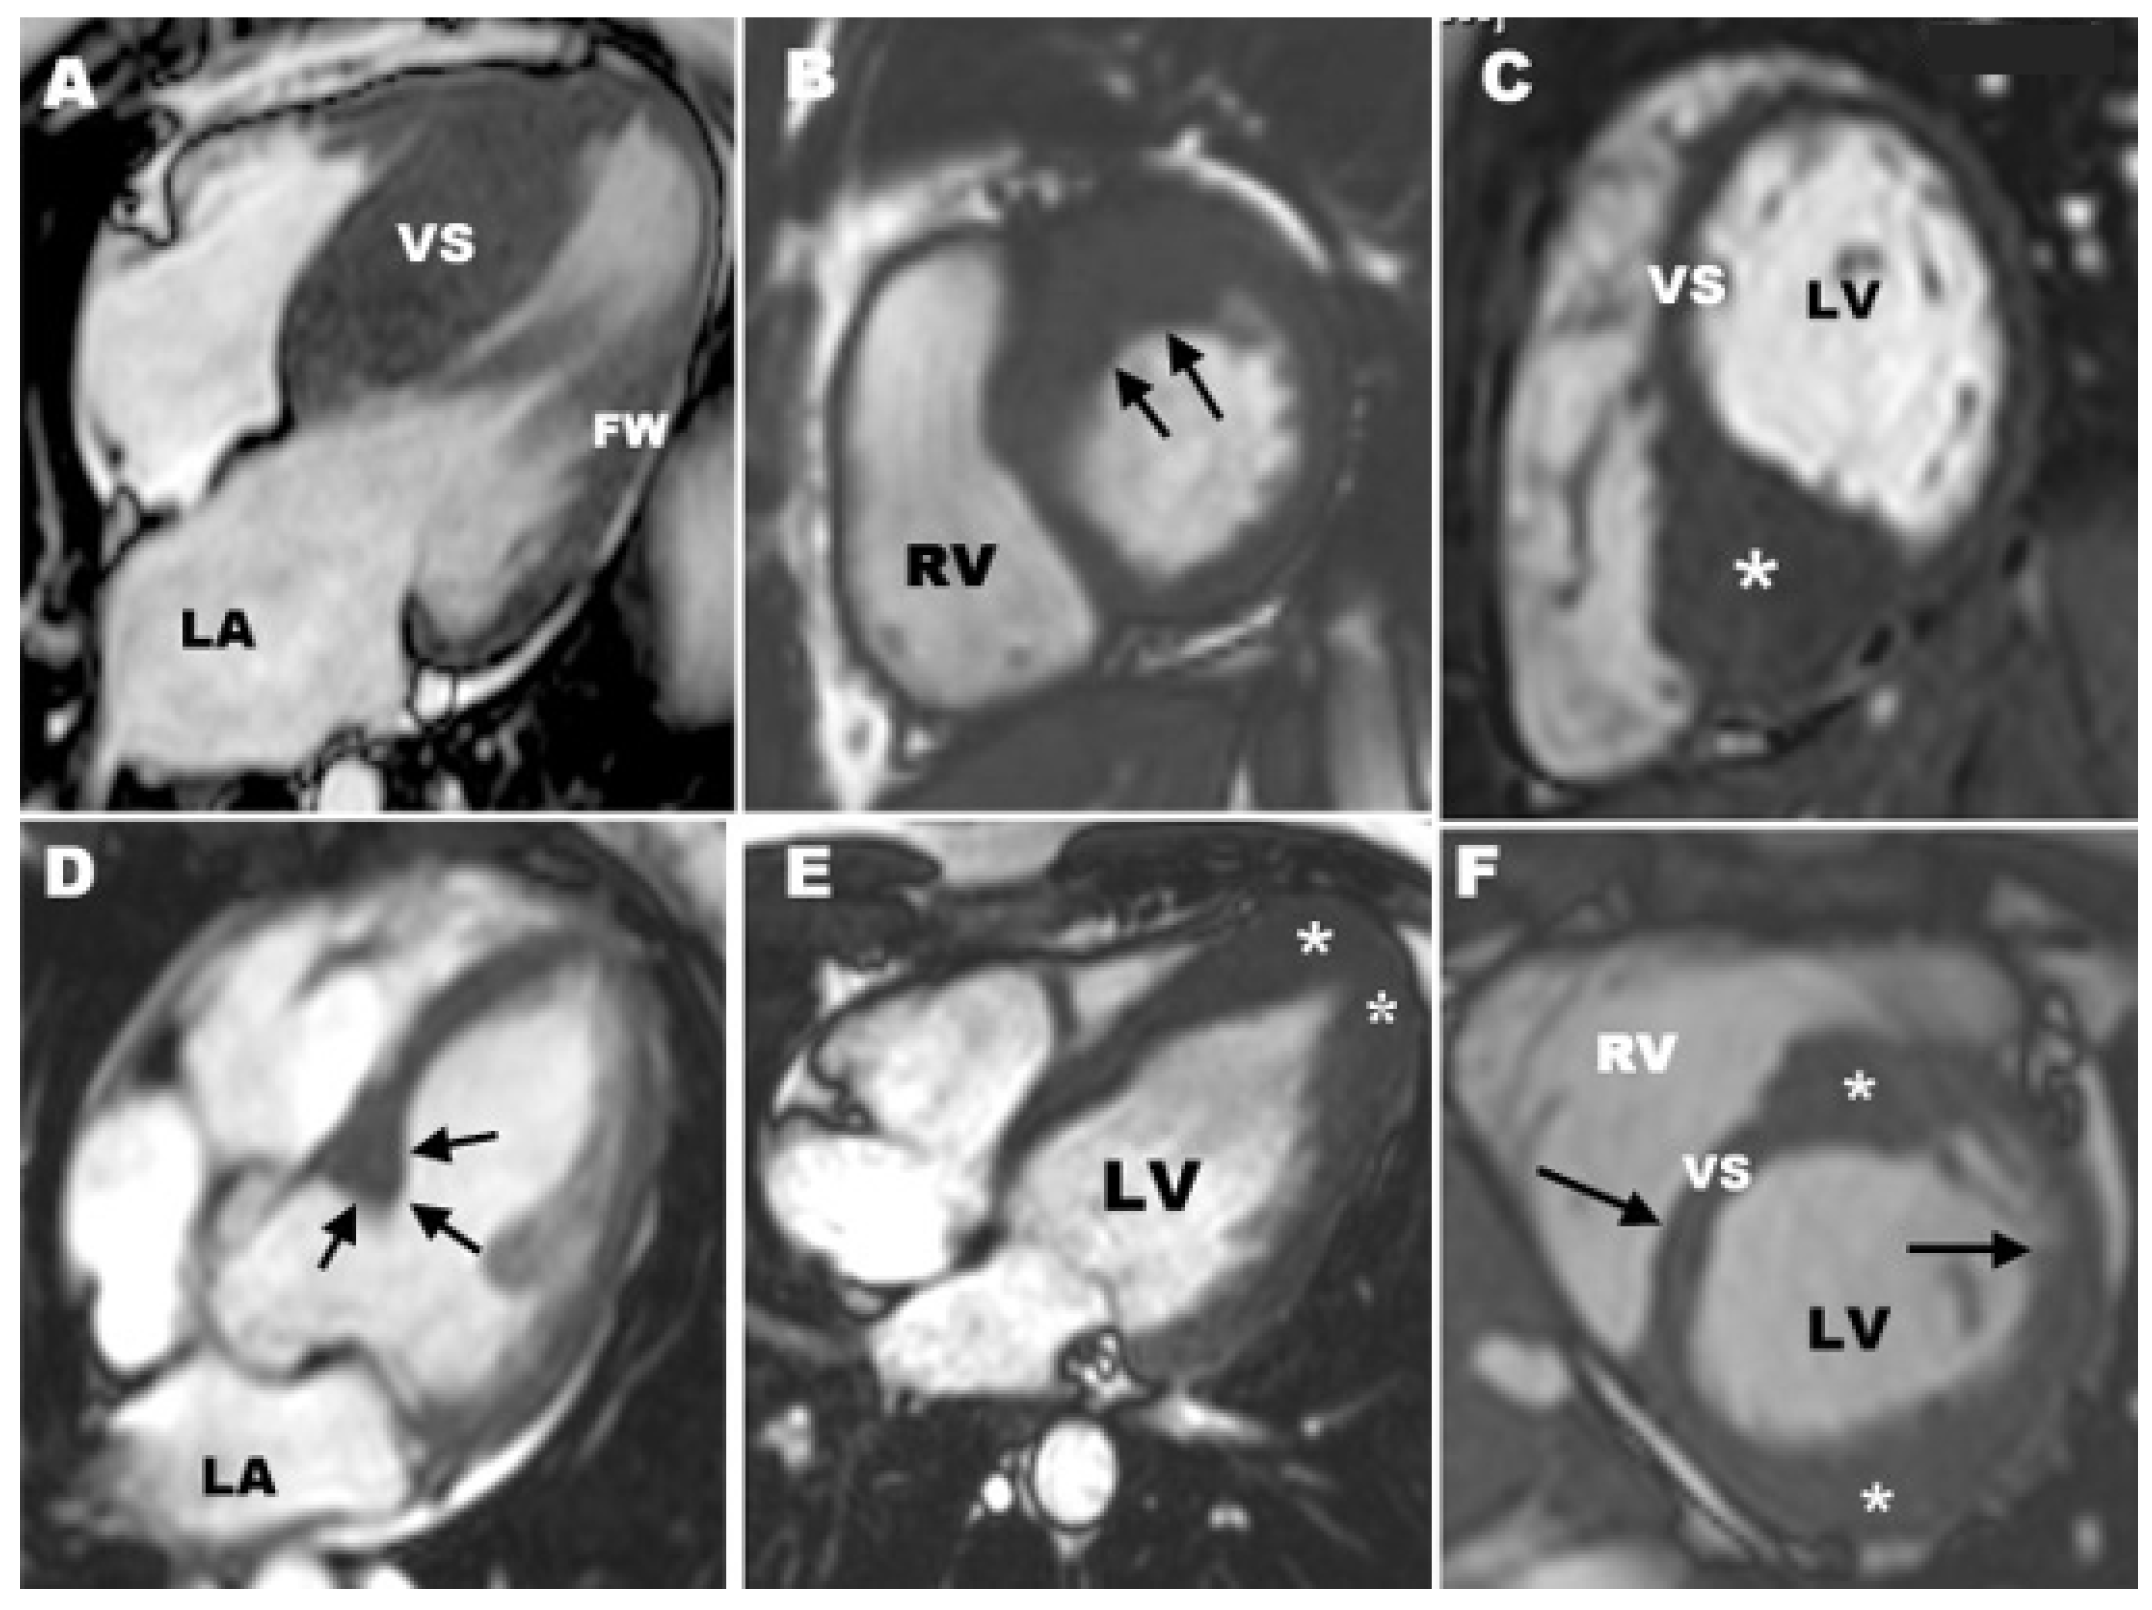

3.1. CMR Evaluation of Apical Hypertrophic Cardiomyopathy

3.2. CMR Evaluation of Focal Hypertrophic Cardiomyopathy

3.3. CMR Evaluation of Midventricular Obstruction

3.4. CMR Evaluation of Apical Aneurysm

3.5. CMR Evaluation of LVOT Obstruction

3.6. CMR Evaluation of Mitral Valve and Papillary Muscles